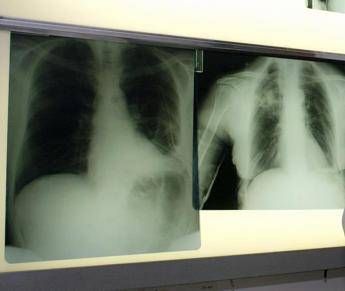

(Adnkronos) – BeOne Medicines, azienda oncologica globale, ha annunciato oggi che la Commissione europea ha approvato tislelizumab in combinazione con chemioterapia a base di etoposide e platino come trattamento di prima linea dei pazienti adulti con tumore del polmone a piccole cellule di stadio esteso (Es-Sclc). "Il tumore del polmone a piccole cellule in stadio esteso è notoriamente difficile da trattare per la sua natura aggressiva e necessita di nuove opzioni terapeutiche – afferma Silvia Novello, presidente di Women against Lung Cancer in Europe (Walce), direttore Oncologia medica all'Ospedale San Luigi Gonzaga di Orbassano e professore ordinario di Oncologia medica all'Università degli Studi di Torino – I risultati dello studio Rationale-312 mostrano che tislelizumab più chemioterapia ha migliorato la sopravvivenza rispetto al trattamento con placebo più chemioterapia, evidenziando la capacità di offrire migliori risultati per i pazienti eleggibili". L'approvazione nel tumore del polmone a piccole cellule di stadio esteso (Es-Sclc) – riporta una nota – si basa sui risultati di Rationale-312 (NCT04005716), uno studio multicentrico di fase 3 randomizzato, in doppio cieco, controllato con placebo, mirato a valutare l'efficacia e la sicurezza di tislelizumab in combinazione con platino (cisplatino o carboplatino a scelta dell’investigatore) più etoposide, come trattamento di prima linea dei pazienti adulti con Es-Sclc. Lo studio, che ha randomizzato 457 pazienti, ha raggiunto l'endpoint primario, mostrando un miglioramento statisticamente significativo e clinicamente rilevante della sopravvivenza globale (Os) con tislelizumab in combinazione con chemioterapia, rispetto a placebo più chemioterapia nella popolazione intent-to-treat (Itt). Come riportato sul 'Journal of Thoracic Oncology', all'analisi finale prevista dal protocollo la sopravvivenza mediana è risultata di 15,5 mesi per tislelizumab con chemioterapia rispetto a 13,5 mesi per placebo più chemioterapia, con una riduzione del 25% del rischio di morte. Tislelizumab più chemioterapia è stato generalmente ben tollerato e non sono stati identificati nuovi segnali di sicurezza. "In meno di 2 anni, tislelizumab è stato approvato in 4 patologie distinte nell'Ue, sottolineando la sua capacità di produrre miglioramenti della sopravvivenza clinicamente significativi e un profilo di sicurezza ben caratterizzato in vari tipi di tumori – dichiara Mark Lanasa, Chief Medical Officer, Solid Tumors in BeOne Medicines – La nostra comprovata esperienza con le registrazioni di tislelizumab in 45 Paesi rafforza il nostro impegno a offrire trattamenti innovativi al maggior numero possibile di persone affette da cancro". L'approvazione – prosegue la nota – si basa anche sui dati di sicurezza aggregati provenienti da più di 3.900 pazienti trattati con tislelizumab sia in monoterapia (n=1.952) che in combinazione con chemioterapia (n=1.950) al regime di dosaggio approvato. Le reazioni avverse più comuni di grado 3 o 4 (≥ 2%) con tislelizumab in combinazione con chemioterapia sono state neutropenia, anemia, trombocitopenia, iponatriemia, ipocalcemia, fatigue, polmonite, linfopenia, eruzione cutanea, diminuzione dell’appetito, aumento di aspartato aminotransferasi, e aumento di alanina aminotransferasi. Oltre al tumore del polmone a piccole cellule di stadio esteso, tislelizumab è approvato nell'Ue per 3 indicazioni nel tumore del polmone non a piccole cellule (Nsclc) nei setting di prima e seconda linea, come trattamento di prima linea dei pazienti eleggibili con carcinoma esofageo a cellule squamose non resecabile (Escc), nell'adenocarcinoma gastrico o della giunzione gastroesofagea (G/Gej) in combinazione con chemioterapia, e come trattamento di seconda linea nel carcinoma esofageo a cellule squamose localmente avanzato o metastatico, non resecabile dopo una precedente chemioterapia a base di platino. —salutewebinfo@adnkronos.com (Web Info)

Cancro polmone a piccole cellule, ok Ue a tislelizumab